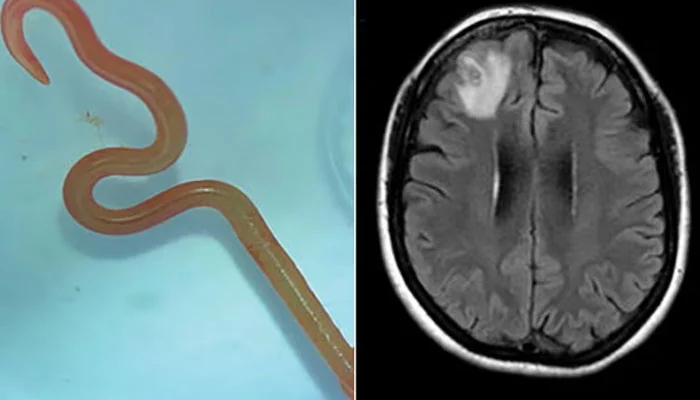

8cm python roundword pulled out from woman’s brain.

A live snake roundworm has been extracted from a woman’s brain, which has stunned the medical community.

Dr. Hari Priya Bandi, the neurosurgeon who performed the treatment, was taken aback when she extracted an 8cm-long parasitic roundworm from the patient’s brain.

The expert recognised the living worm as the Ophidascaris robertsi roundworm, which is typically found in pythons.

Surprisingly, this was the first time this parasite had been detected in people.